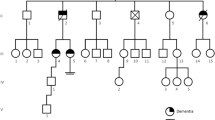

Figure 4 summarizes the genetic and CSF features of the patients.

Biomarkers results. In the upper panel, the main results of genetic and CSF analyses are shown (APP amyloid precursor protein gene, PSEN1 and 2 presenilin 1 and 2 genes, APO E apolipoprotein E, NP not present). In the lower panel, the karyotypes of patients 4 and 5 are shown, as well as T-tau, Aβ1-42, and P-tau(181-P) in patients 4 and 7. The IATI (INNOTEST Amyloid Tau Index) is defined as Ab1-42/(240 + 1.18 × T-tau). The red line in the upper chart indicates IATI = 1

All patients showed a complete trisomy 21.

Mutations were ruled out by sequencing the APP, PSEN1, and PSEN2 genes in all patients.

No subject was homozygosus for the type 4 APOE allele (ε4/ε4). Homozygosity APOE ε3/ε3 was observed in all patients.

In patients 4 and 7, the CSF Aβ42 was 565 and 235.8 pg/ml (normal range 499–1,088), p-tau181 was 94.10, and 70.90 pg/ml (normal value <33), t-tauAg was 954 and 1,409.30 ng/ml (normal value <300), and Aβ42/p-tau181 ratio was 6 and 3.3 (normal value >7), respectively. Using ROC curve analyses, the CSF Aβ42 and p-tau181 values in these patients met the requirements for clinical use in discriminating Alzheimer’s disease from normal aging and other specific neurological disorders [25].